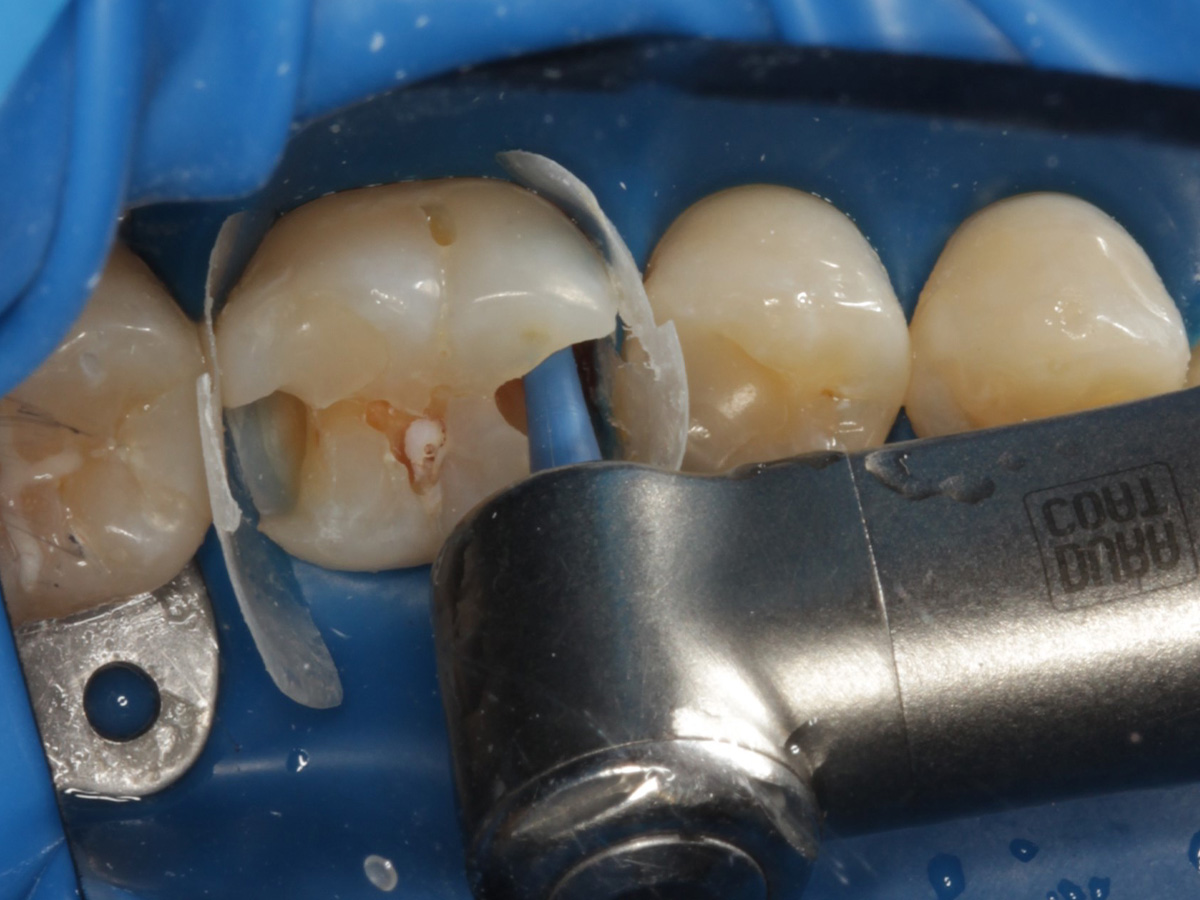

Abbildung 5

Kariesexcavation pulpennah mit Kunststoffrosenbohrer

Abbildung 6

Reinigung der Kavitäten mit Microetcher